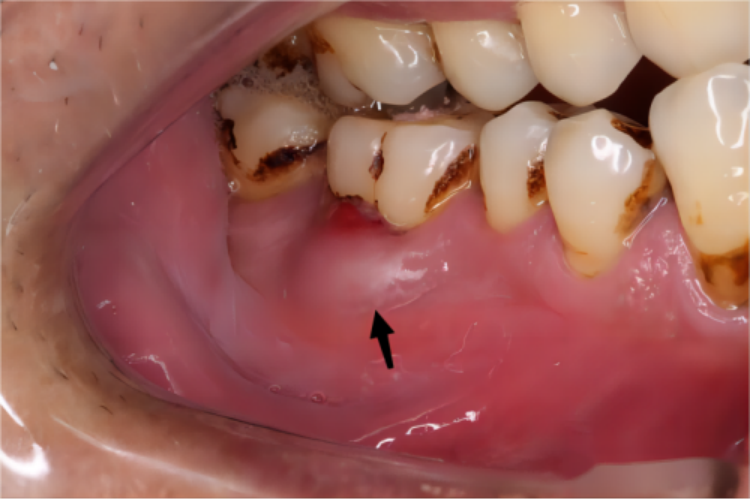

急性化脓性根尖周炎患者病情进展至黏膜下脓肿期时,在门牙上的根尖区牙龈黏膜出现局限的肿胀,呈半球形隆起,触摸有明显波动感,脓肿较表浅而易破溃。此时牙龈内的压力紧绷感、自发性胀痛和咬合痛都不再剧烈,但仍感觉患牙轻微松动。